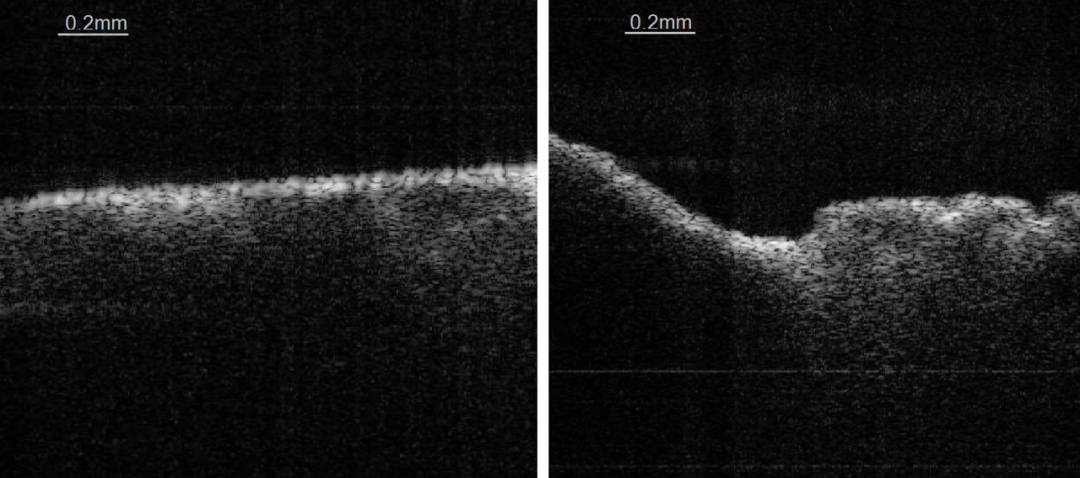

不同于其他医疗光学影像设备厂商采用的CT、MRI、超声等传统光学影像技术,益英光电尝试采用国际前沿的光学相干层析技术(简称:OCT技术)为设备的底层技术,该技术可通过激光扫频获取精准人体组织断层影像,且拥有非侵入、非接触、高分辨率、高灵敏度等特点,十分适合辅助精密的脑外科手术的开展。

益英光电以激光光学相干层析成像( Optical Coherence Tomography,OCT)技术为基础,与四川大学华西医院、电子科技大学合作研究超视觉成像及标定方法。首创手术智能实时图像处理、标定病理组织的医疗手术器械,用于神经外科技手术中辅助医生对病理组织区域进行精确定位,达到实时、精准、微创的手术目标,在减少医生确定手术时的精准性、减少病人生理功能受损度方面具有明显的技术优势,也是机器人精准手术系统的前端超视觉实时成像的“眼睛”,因此其技术特性就注定在精准医疗中的决定性定位。 目前处于样机实验阶段,设备原理机已完成测试,效果达到技术需求,目前在研机型主要针对二期实验动物及人机工程学进行,以期达到三类诊断器械的应用水平。